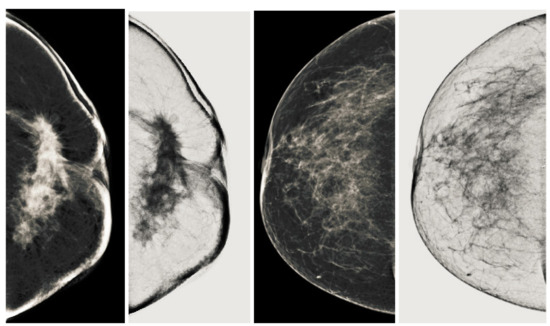

5.1. Analysis of Proposed Image Enhancement Technique

We also measured the PSNR, the image contrast, and the EME of each category of databases, as we analyzed the image in terms of visual observation. The Table 3 shows the performance of our proposed image enhancement method. It can be seen from the Table 3 that our proposed method improved PSNR, contrast, and EME, and this also shows that our method can work on every category of BI-RADS. Because many techniques do not work on higher grade BI-RADS due to the complexity and the images are not of good quality. We obtained an average improvement in PSNR, contrast, and EME in the Table 4. For more observations, we analyzed the visual image of each category and we analyzed the CC and MLO of each category as shown in the Figure 7, Figure 8, Figure 9, Figure 10, Figure 11, Figure 12, Figure 13, Figure 14, Figure 15 and Figure 16. From the figures, every detail of image of every category can be observed, leading to better segmentation of the abnormal region. This image enhancement technique can be used as preprocessing steps for the detection of breast cancer. It is a very fast processing algorithm and it takes on 21.13 s. It gives opportunity to medical experts to analyze the mammogram images very quickly to propose the timely treatment.

Figure 7.

Analysis of CC view of BI-RADS-1 mammogram images.

Figure 8.

Analysis of MLO view of BI-RADS-1 mammogram images.

Figure 9.

Analysis of CC view of BI-RADS-2 mammogram images.

Figure 10.

Analysis of MLO view of BI-RADS-2 mammogram images.

Figure 11.

Analysis of CC view of BI-RADS-3 mammogram images.

Figure 12.

Analysis of MLO view of BI-RADS-3 mammogram images.

Figure 13.

Analysis of CC view of BI-RADS-4 mammogram images.

Figure 14.

Analysis of MLO view of BI-RADS-4 mammogram images.

Figure 15.

Analysis of CC view of BI-RADS-5 mammogram images.

Figure 16.

Analysis of MLO view of BI-RADS-5 mammogram images.